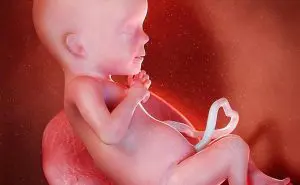

妊娠12週目の母体と胎児の変化|ダウン症の兆候【医師監修】

妊娠13週目の変化とダウン症の可能性もわかるNIPT(新型出生前…